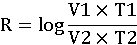

- доза, вызывающая гибель 50% животных

- доза, вызывающая гибель 50% животных